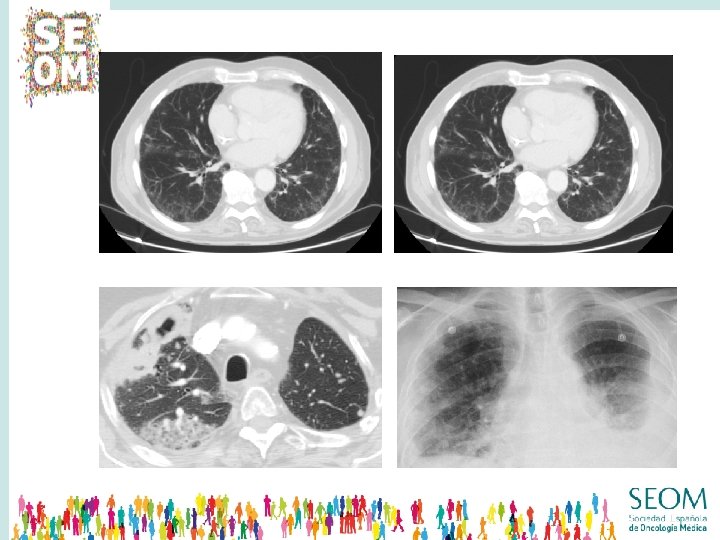

NEUMONITIS Grado 1: hallazgo radiológico Grado 2: Tos seca + Disnea Grado 3: Insuficiencia respiratoria Grado 4: Compromete la vida 2 -6% Grado 2 -3 Neumonitis fatal 0. 7% § Rx tórax § TAC § FBC + bx pulmonar

SOSPECHA DE NEUMONITIS DIAGNÓSTICO DIFERENCIAL INFECCIÓN RESPIRATORIA LINFANGITIS GRADO 1 GRADO 2 � SUSPENDER TTO Valorar REINICIAR TTO 100% dosis HOSPITALIZAR -- -- CORTICOTERAPIA -- 0. 5 -1 mg/Kg/d OTRO INMUNOSUPRESOR -- -- GRADO 3 � Dosis � GRADO 4 � No � 1 -2 mg/Kg/d -- Infliximab Micofenolato Eur J Cancer 2016; 60: 210